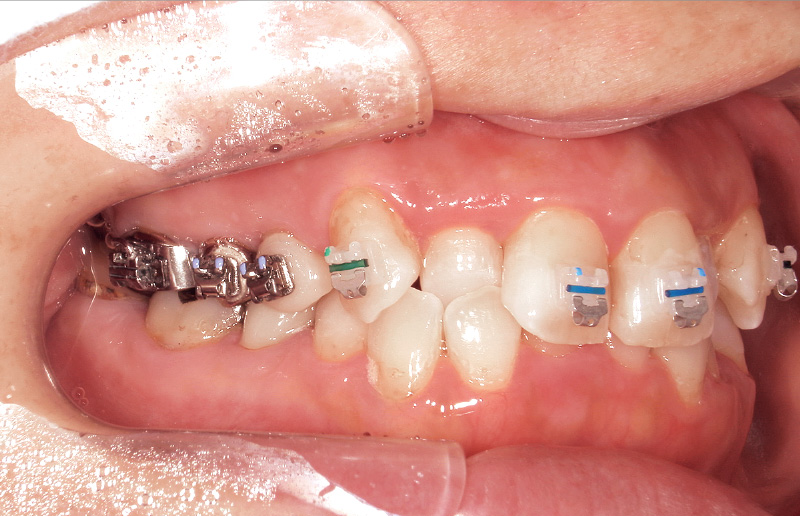

基本構成が「スーパーボンド」と非常に近いため、前処理材も「スーパーボンド」と同様である。エナメル質にはセルフエッチングプライマーである「ティースプライマー」(図6)や従来のリン酸エッチング材も使用可能である。ブラケット装着の場合、必要部位にのみ最小限の酸処理をしたいため、筆者はジェル状のリン酸エッチング材である「表面処理材 高粘度レッド」を選択している(図7)。セラミックス、ハイブリッドレジン、金属などの歯質以外の被着体には、全ての修復材料に適用できる「M&Cプライマー」を使用する。

使用方法は「スーパーボンド」と同様であるが、「ボンドフィルSBⅡ」の特徴的な点は粉液比にあり、「キャタリストV」1滴に対し液材3滴の割合で使用する(図8)。被着体ごとの適切な前処理を行った後、筆積法を用いてブラケットを被着面に圧接し、はみ出した余剰レジンを除去する。次に光照射を行い、最低3分以上経過後に十分な重合を確認してからワイヤーを装着する(図9~12)。ただし、「スーパーボンド」および「ボンドフィルSBⅡ」は最終的な硬化が完了するまでに24時間を要するとされている。特にジルコニア冠やCAD/CAMレジン冠などはブラケット脱離が多いことが報告されているため、接着強さおよび重合率が最大になる24時間経過後にワイヤーを装着することで、ブラケット脱離のリスクを軽減できると考えている。